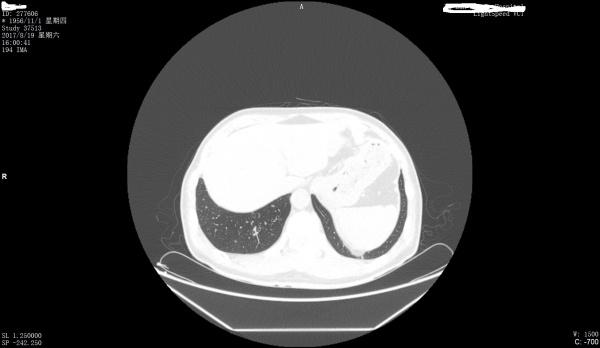

看看是否左膈肌出现胸腹膜裂孔疝

最好把纵膈窗也传一下

第一上传图片少,第2目前来看只能是疑似。